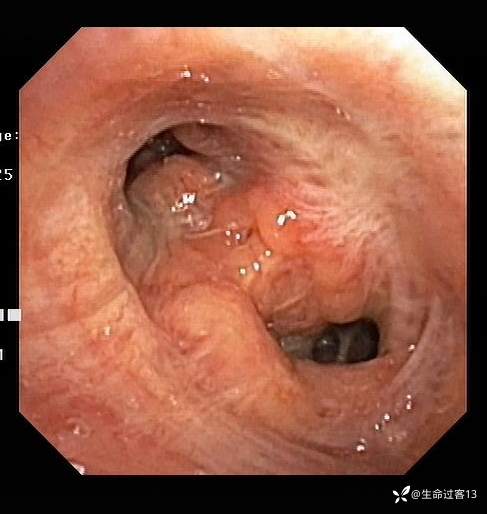

后行纤维支气管镜,如下:右上叶开口变异(未探及右上叶尖段开口);左主支气管远端1-5点钟方向及左上叶开口粘膜突起、肥厚增生,表面粗糙、凹凸不平,左上固有叶、舌叶开口狭窄、粘膜肥厚,其亚段窥探不清,左下叶开口通畅、粘膜光滑,双侧支气管散在碳末沉积。于左上叶(固有叶、舌叶)灌洗(灌洗量60ml,回收量50ml),灌洗液浑浊含痰液(送检培养+药敏、抗酸染色、脱落细胞、结核菌培养、Xpert),于左上叶开口粘膜肥厚处活检(送检病理)、刷检2次(送检细胞学+细菌学)。